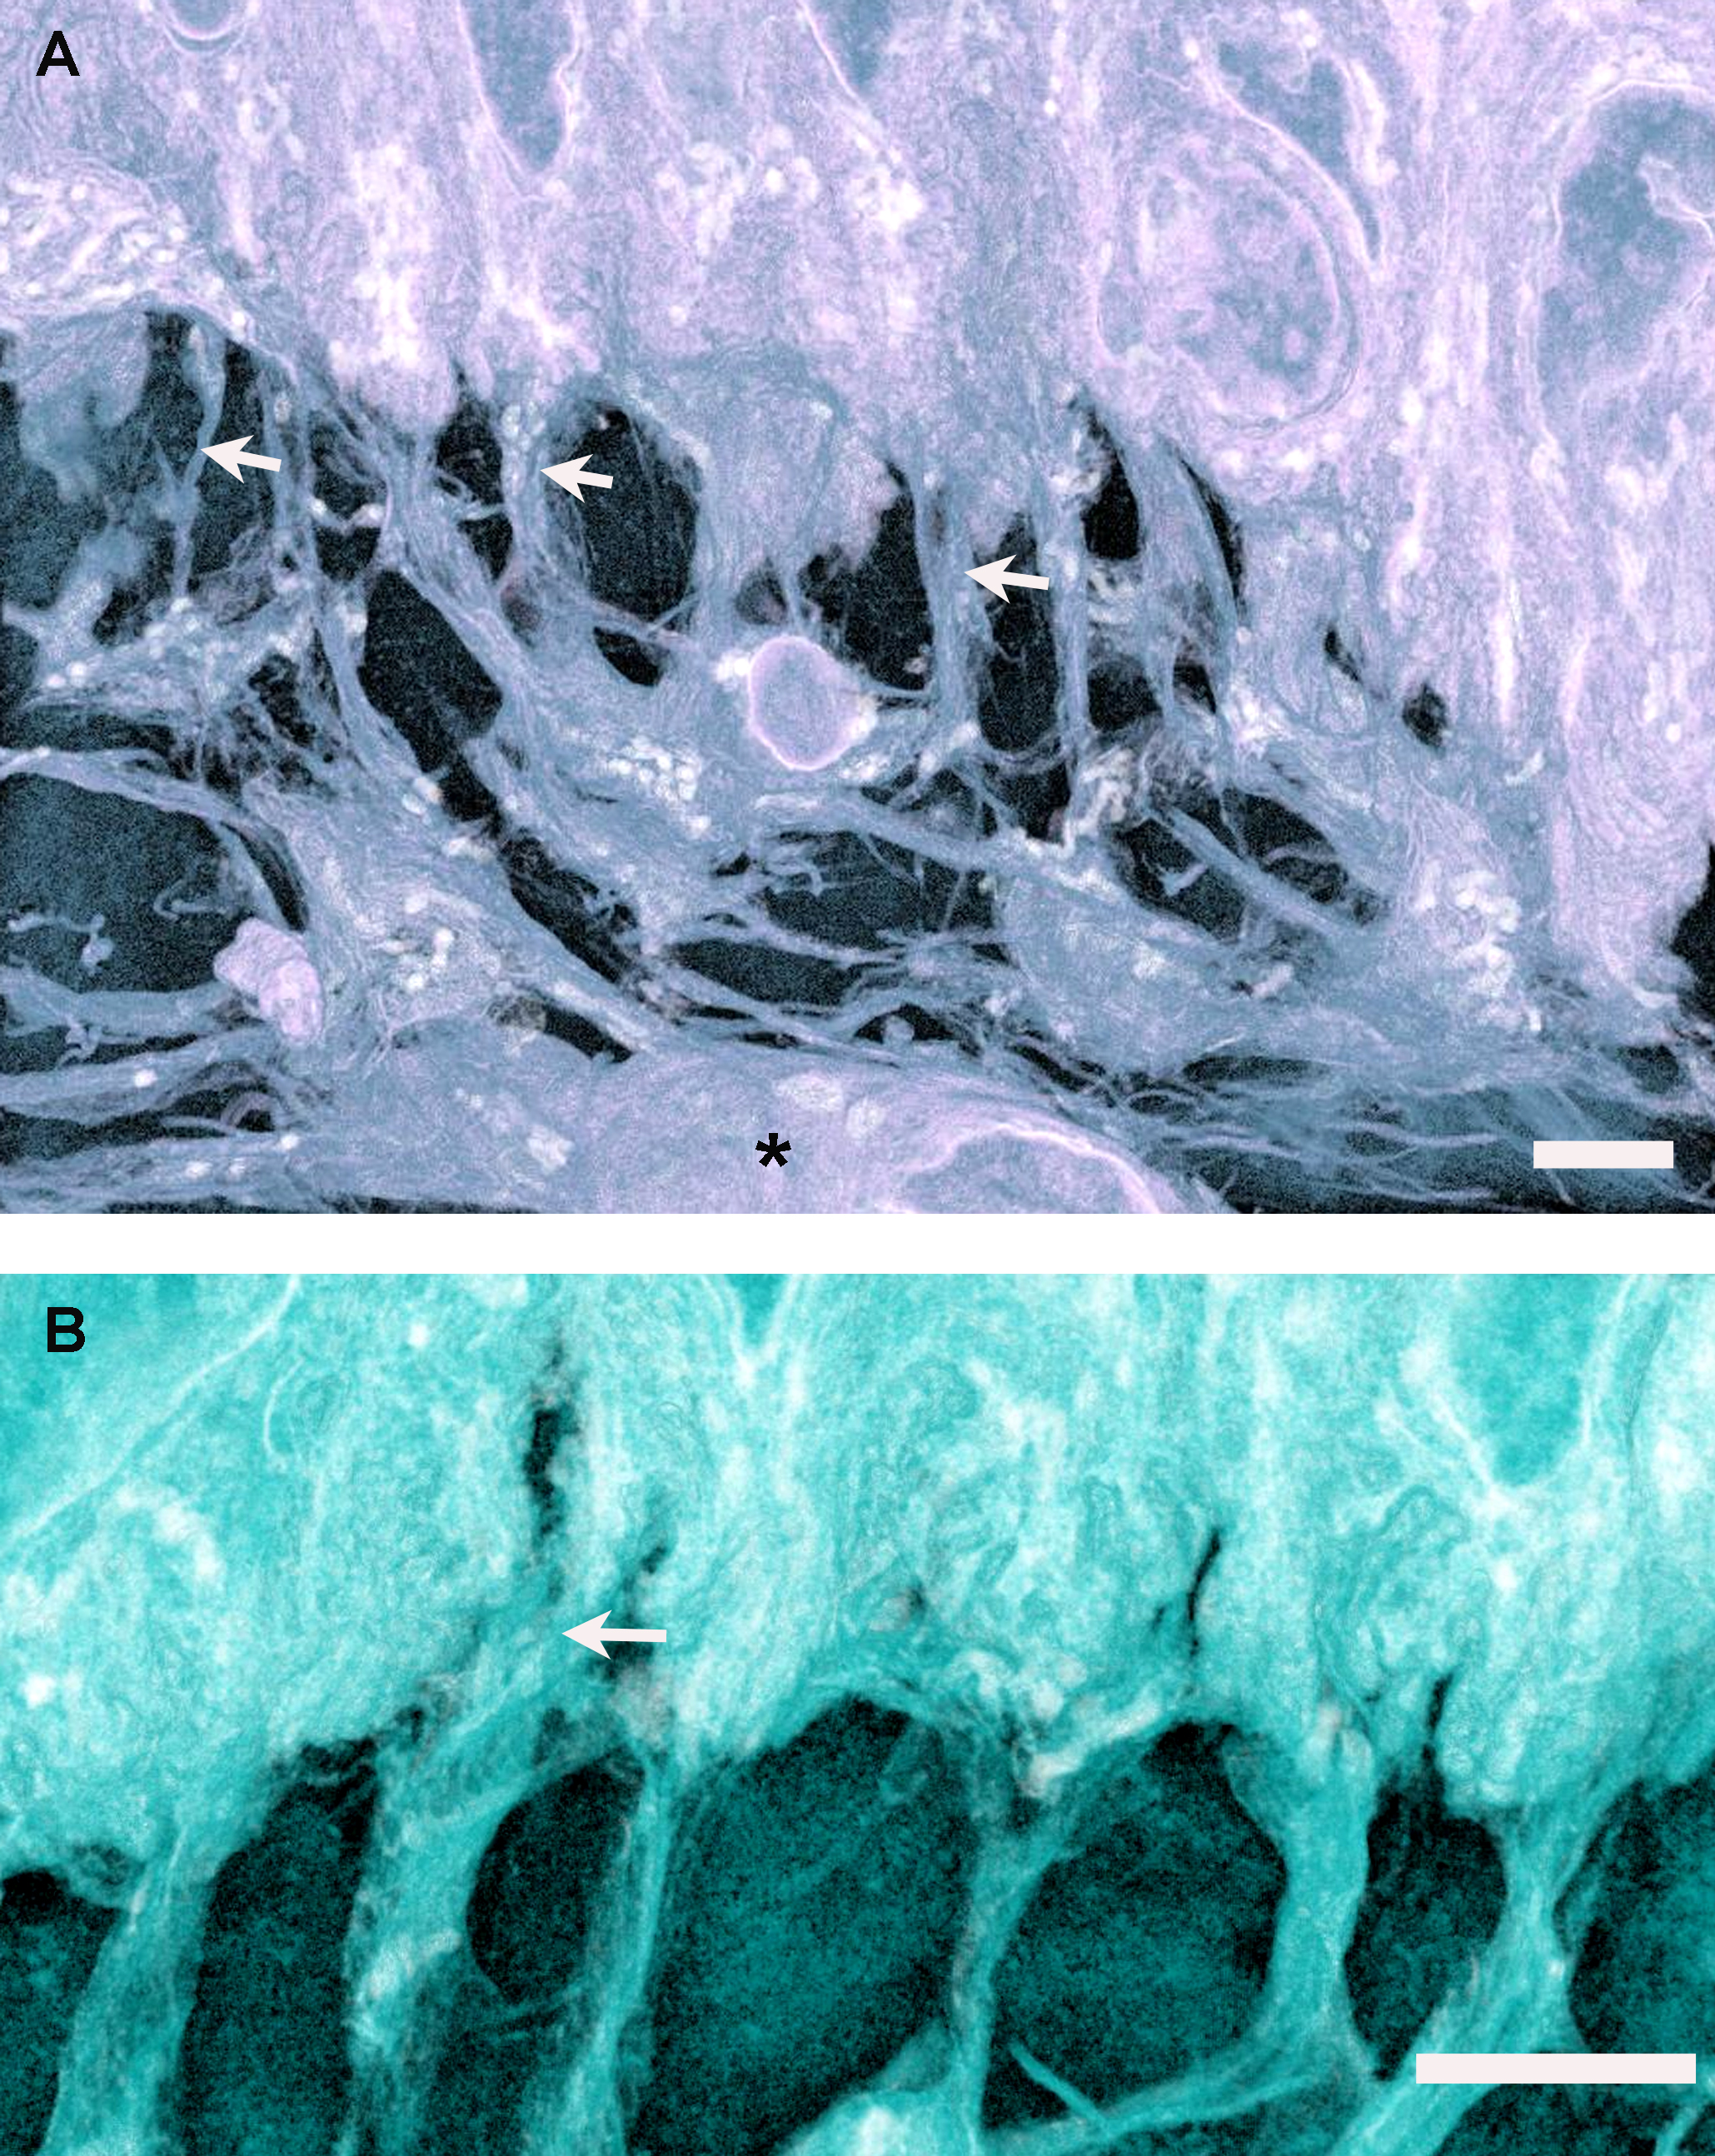

Figure 4. Three-dimensional reconstructions in ImageJ 3D Viewer of the epithelial basement membrane zone of the rabbit limbal cornea

from serial block face scanning electron microscopy. A: A blood vessel can be seen in the superficial stroma (asterisk), below mesenchymal cells that extend numerous cytoplasmic

processes (arrows) distally to contact the basal epithelial cells. The scale bar represents 4 µm. B: Mesenchymal cell processes form diffuse associations with epithelial cells, occasionally appearing to extend between adjacent

cells (arrow). The scale bar represents 4 µm.